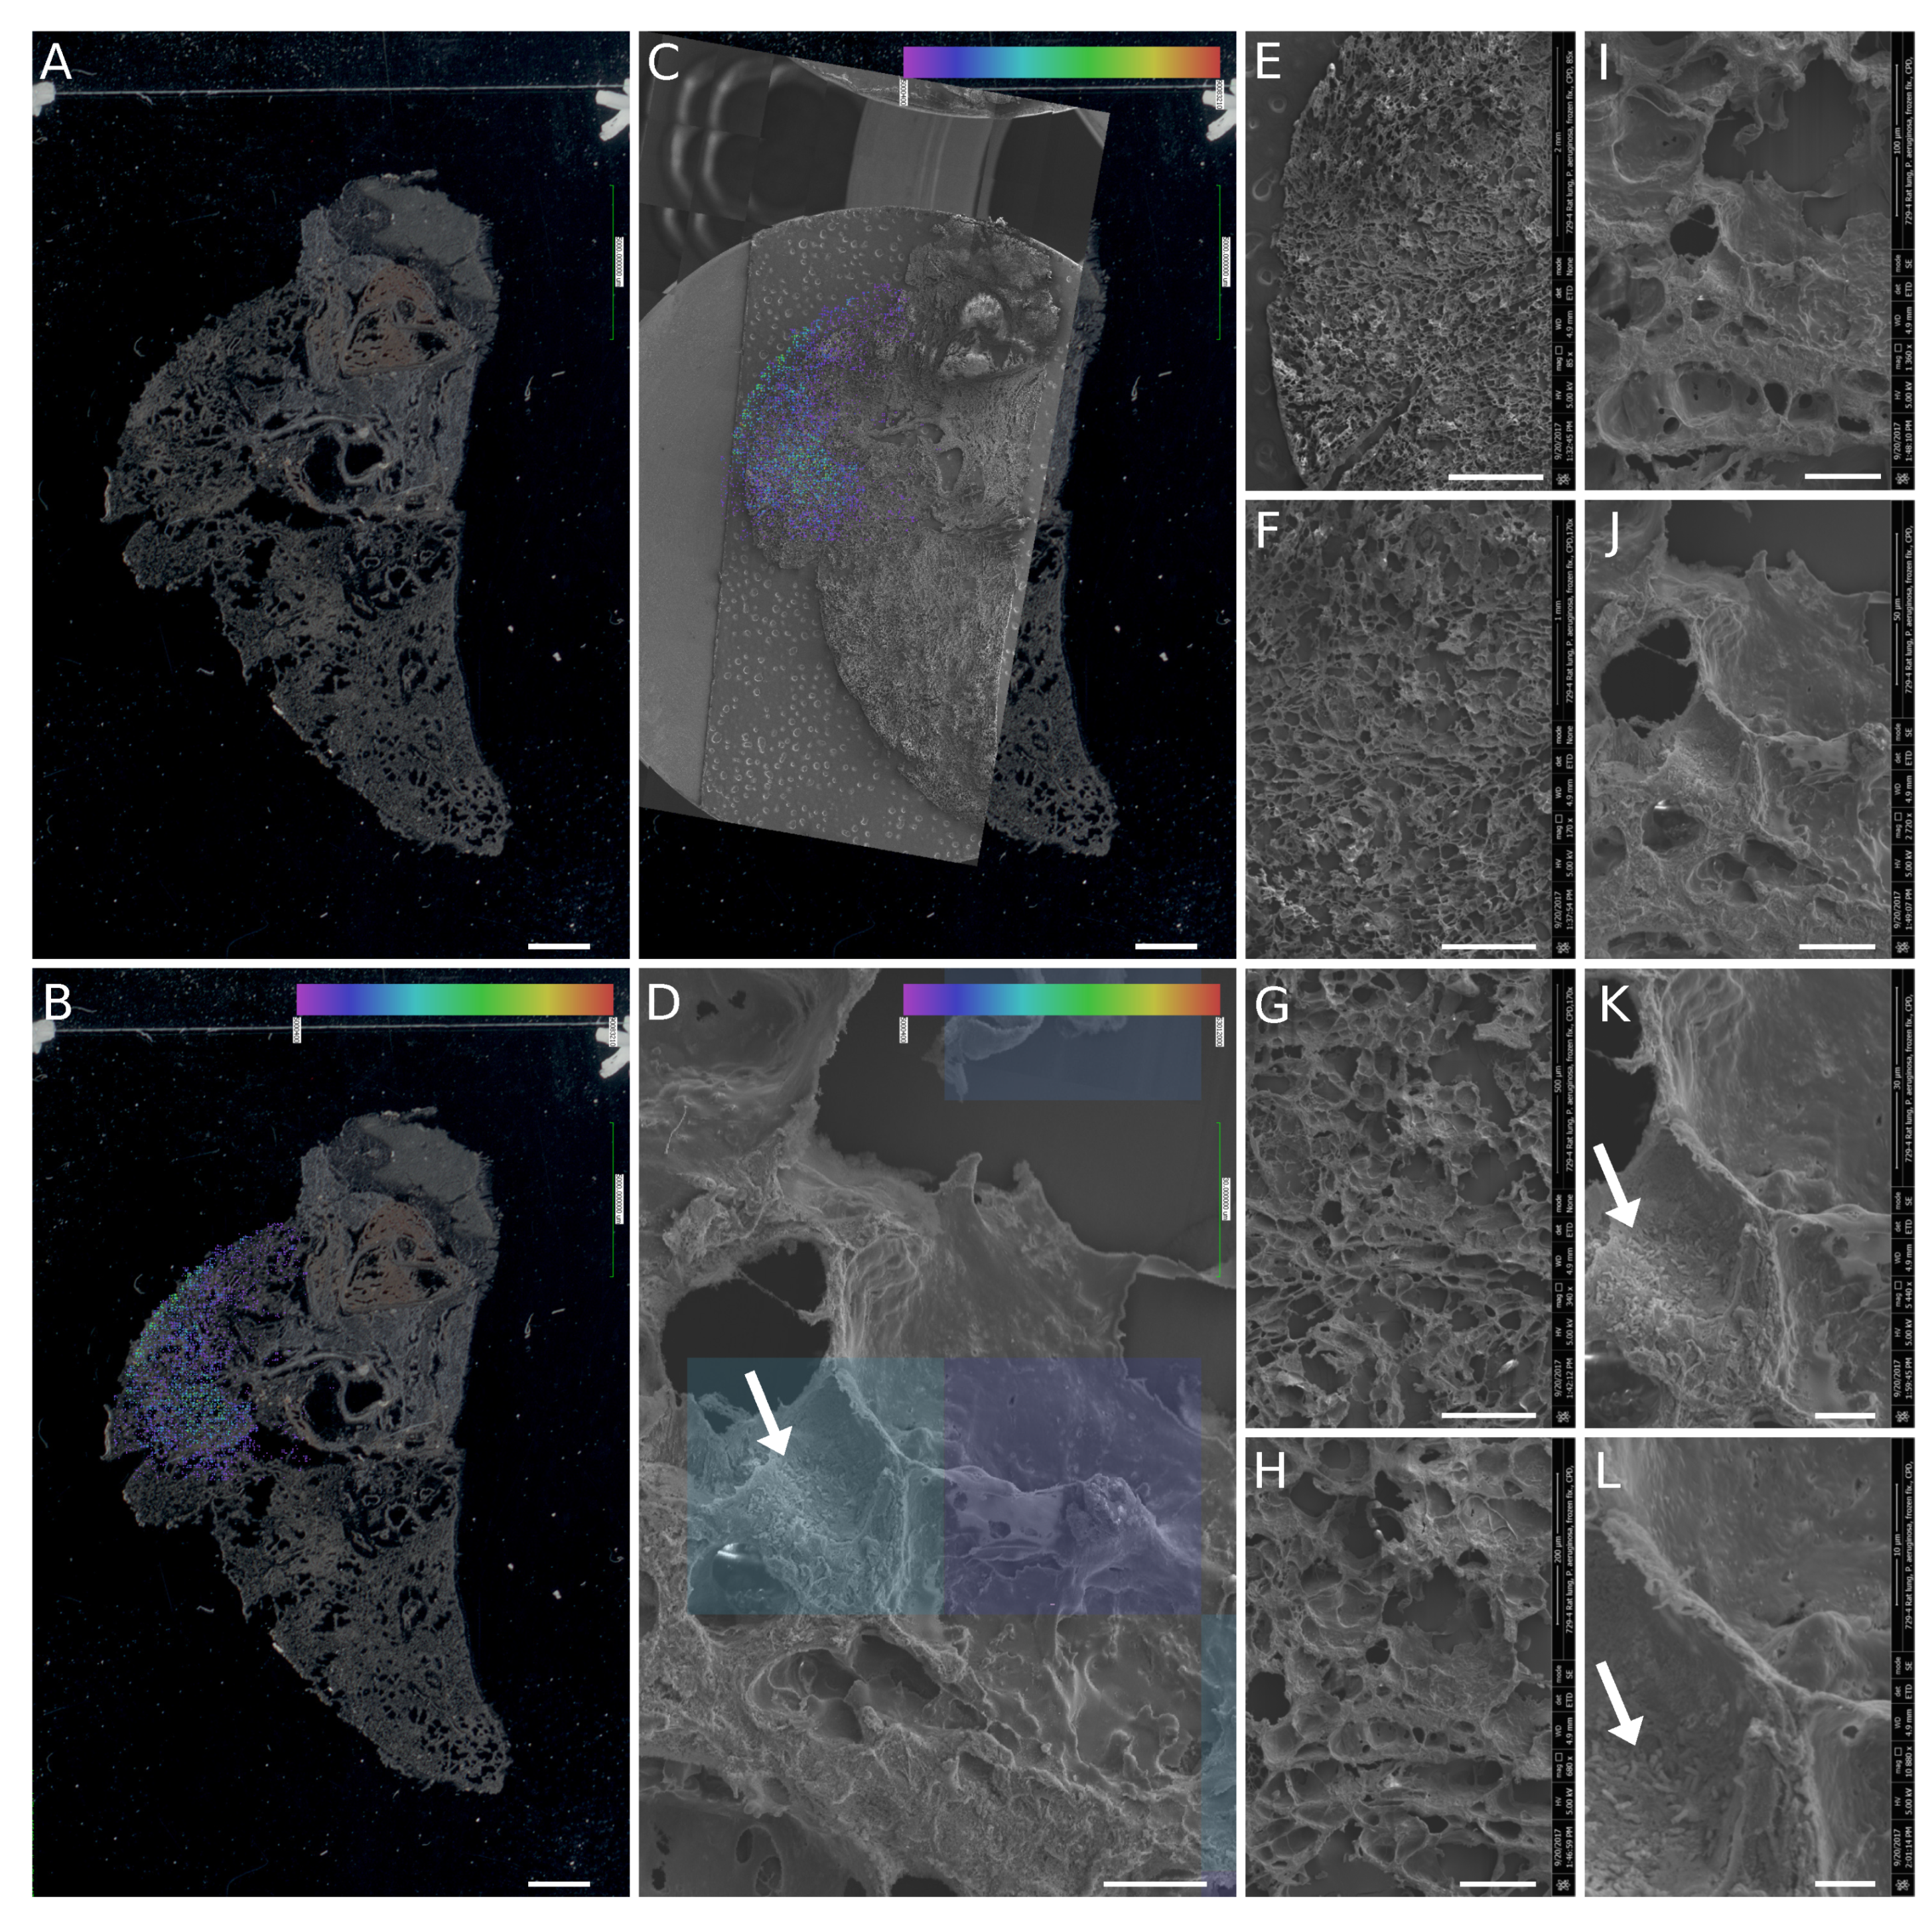

3.4. SEM Imaging of Infected Tissues and Data Fusion with MALDI-MSI